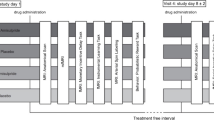

FMRI task: monetary incentive delay

We used event-related fMRI to assess blood-oxygen-level dependent (BOLD) brain activation during the monetary incentive delay (MID) task (Fig. 1) [39]. In short, the MID task was used to evoke anticipation of potential monetary reward, loss or no consequential outcome. It consists of two sessions of 72 trials of 6 s, yielding a total of 144 trials and total duration of 14 min. During each trial, subjects were shown one of seven cues. Cues signaling reward were denoted by circles (n = 54), loss by squares (n = 54) and no monetary outcome by triangles (n = 36). The amount of money that subjects were able to win was indicated by one horizontal line (0.20 Euro), two lines (1.00 Euro) and three lines (5.00 Euros). Similarly, loss cues signalled the possibility of losing the same amounts of money. Subjects had to respond to the white target square that appeared for a variable length of time. To succeed in a trial, volunteers had to press the button during the time that the white square target was visible (target, 160–260 ms). Unlike the MID described by Knutson et al. [35], we did not pay the amount of money earned during the task; reward and loss was based on point scoring [6, 34].